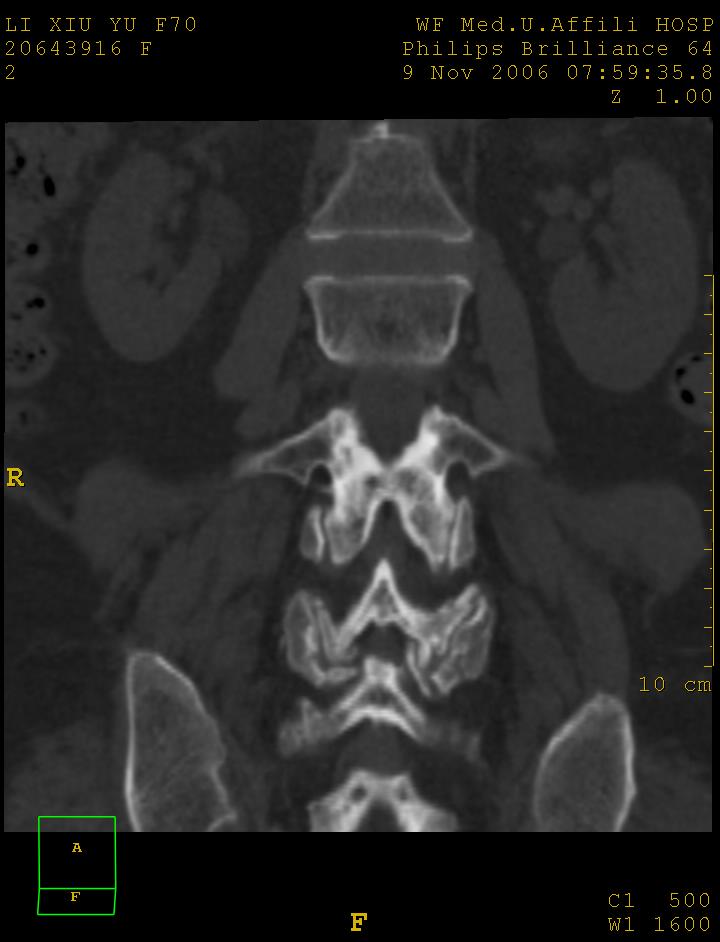

女,70岁,腰痛

1 腰4椎弓崩裂,腰4椎体向前ι度滑脱并椎小关节交锁,腰4/5小关节明显增生硬化,间隙内可见真空征。

2 腰椎间盘不同程度膨出,腰4/5、腰5/骶1椎间盘突出,腰4/5椎间隙变窄,腰5/骶1间盘变性(间隙内可见真空征)。

3 诸椎体缘不同程度骨质增生,腰5、骶1后骨刺明显,腰5椎体后上缘可能有软骨结节(由于没有平扫,不易确定)。

4 椎体前缘可见主动脉壁钙化。

诊断:腰椎退行性骨关节病。